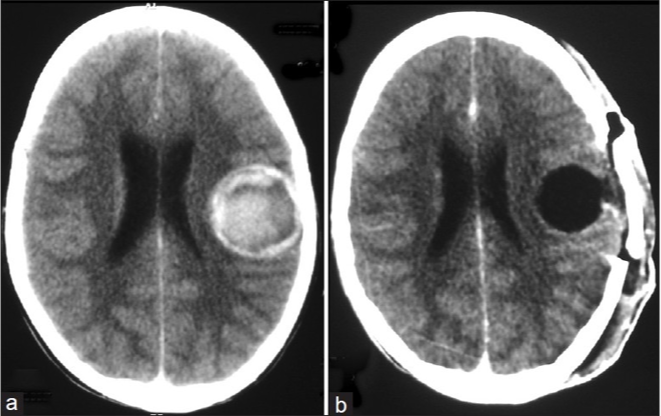

DIAGNOSTICS – MRI Glioblastoma

What does this refer to

Butterfly gliomas

High grade astrocytoma

Usually a glioblastoma

Crosses the midline via the corpus callosum.

May involve other white matter commissures

The term butterfly refers to the symmetric wing-like extensions across the midline.

WORKUP – MRIButterfly Glioma

What does this refer to **PICTURE WILL BE ON EXAM

Butterfly Glioma